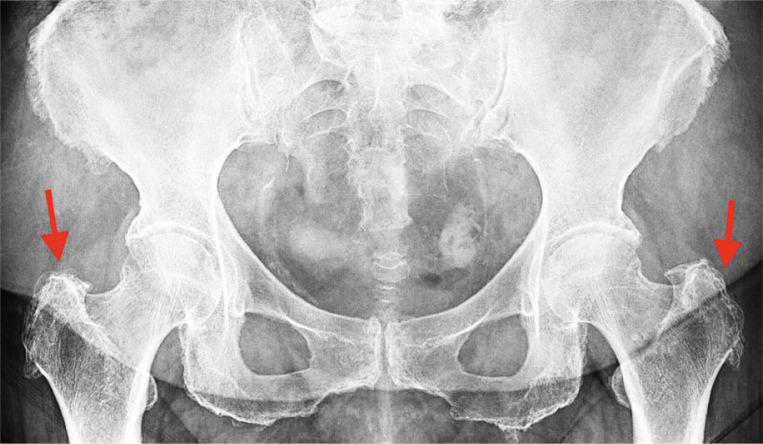

大转子疼痛综合征(GTPS)发生在一大群患者中。这个问题可以影响任何年龄的患者,并且与久坐、超负荷和不符合人体工程学的生活方式/工作方式有关,同时缺乏定期的身体活动。迄今为止的文献描述了各种治疗方法的有效性。使用糖皮质激素注射和物理治疗。其中一种新方法是使用I型胶原蛋白(COL-I)注射胶原蛋白疗法,这是一种源自猪的蛋白质,其目的之一是使炎症改变的肌腱再生。多种修复机制被激活,包括成纤维细胞的诱导和增殖,以及它们向病理部位的迁移。随后是刺激和合成col - 1,分泌和成熟。最终达到再生效果。本文旨在探讨coli作为一种新的治疗手段在GTPS注射治疗中的作用。

Greater trochanter pain syndrome (GTPS) occurs in a large group of patients. This problem can affect patients of any age and is associated with a sedentary, overloading, and non-ergonomic lifestyle/work with a concomitant lack of regular physical activity. The literature to date describes the effectiveness of various therapies. Glucocorticosteroid injections and physical therapy are used. One of the new methods is injection collagen therapy using collagen type I (COL-I), a protein of porcine origin, which aims, among other things, to regenerate inflammation-changed tendon. Various repair mechanisms are activated, including the induction and proliferation of fibroblasts, as well as their migration to the pathological site. This is followed by stimulation and synthesis of COL-I, secretion, and maturation. Ultimately, a regenerative effect is achieved. This article aims to discuss the role of COL-I in the injectable treatment of GTPS as a new therapeutic approach.